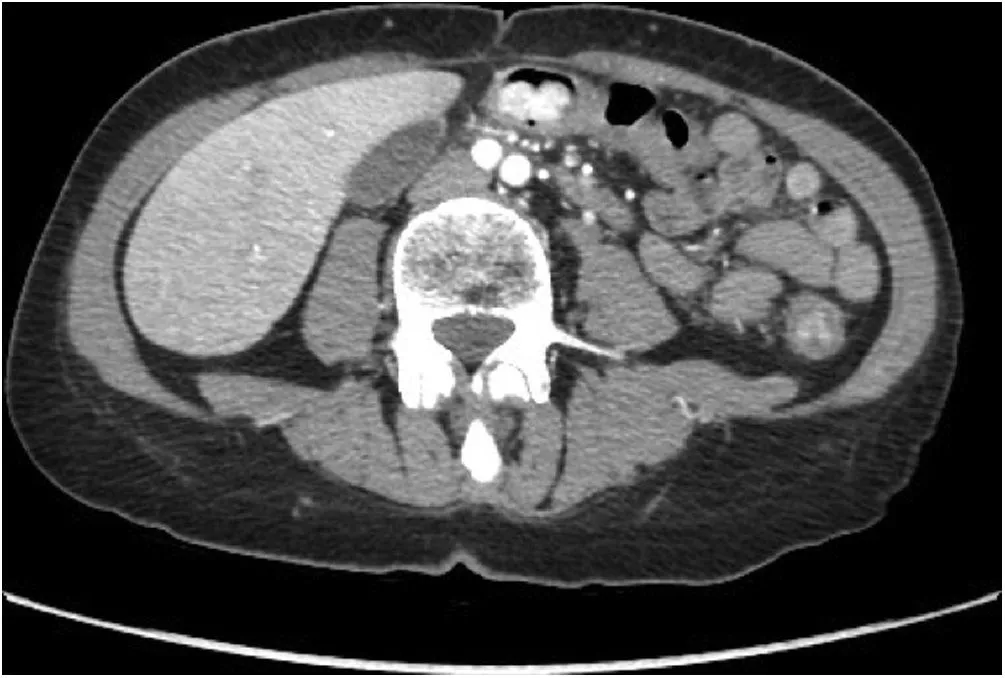

При эндоскопическом исследовании толстая кишка имела вид трубы с диффузной гиперемией, эрозиями слизистой и двухсантиметровым полипоидным поражением с нерегулярной формой на уровне поперечной ободочной кишки. Гистопатологическое исследование биоптатов выявило мезенхимальное новообразование с неопределенными признаками злокачественности. В ходе рентгенокомпьютерной томографии органов брюшной полости с болюсным усилением обнаружено неоднородное гиподенсированное образование 2,5 × 1,6 см в диаметре с интенсивным усилением в артериальной фазе, локализованное в поперечной ободочной кишке (рис. 1).

Рисунок 1 [1].